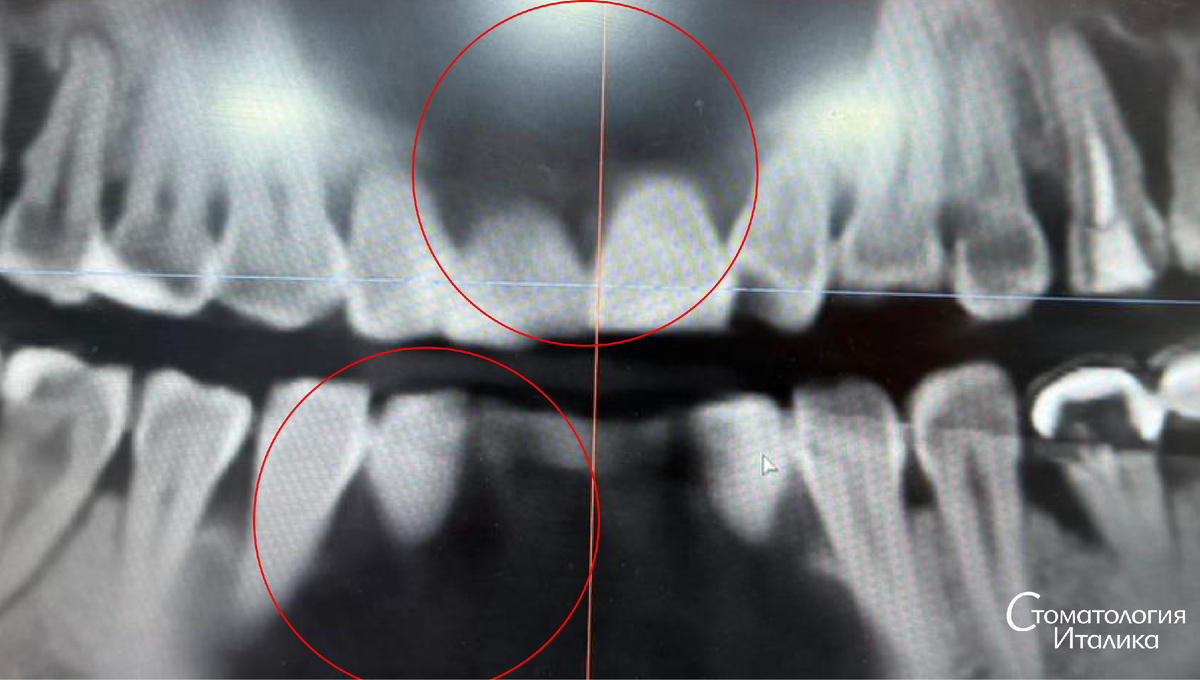

Главное доказательство – контрольный снимок через 6 месяцев

Второй рентген, сделанный спустя полгода, показывает изменения, которые невозможно подделать:

• костная ткань восстановилась

• глубина дефектов уменьшилась

• зубы получили нормальную опору

• воспаление ушло

Пациент получил не импланты, а собственные сохранённые зубы, которые ещё долго будут служить.

наглядное до/после нашего пациента